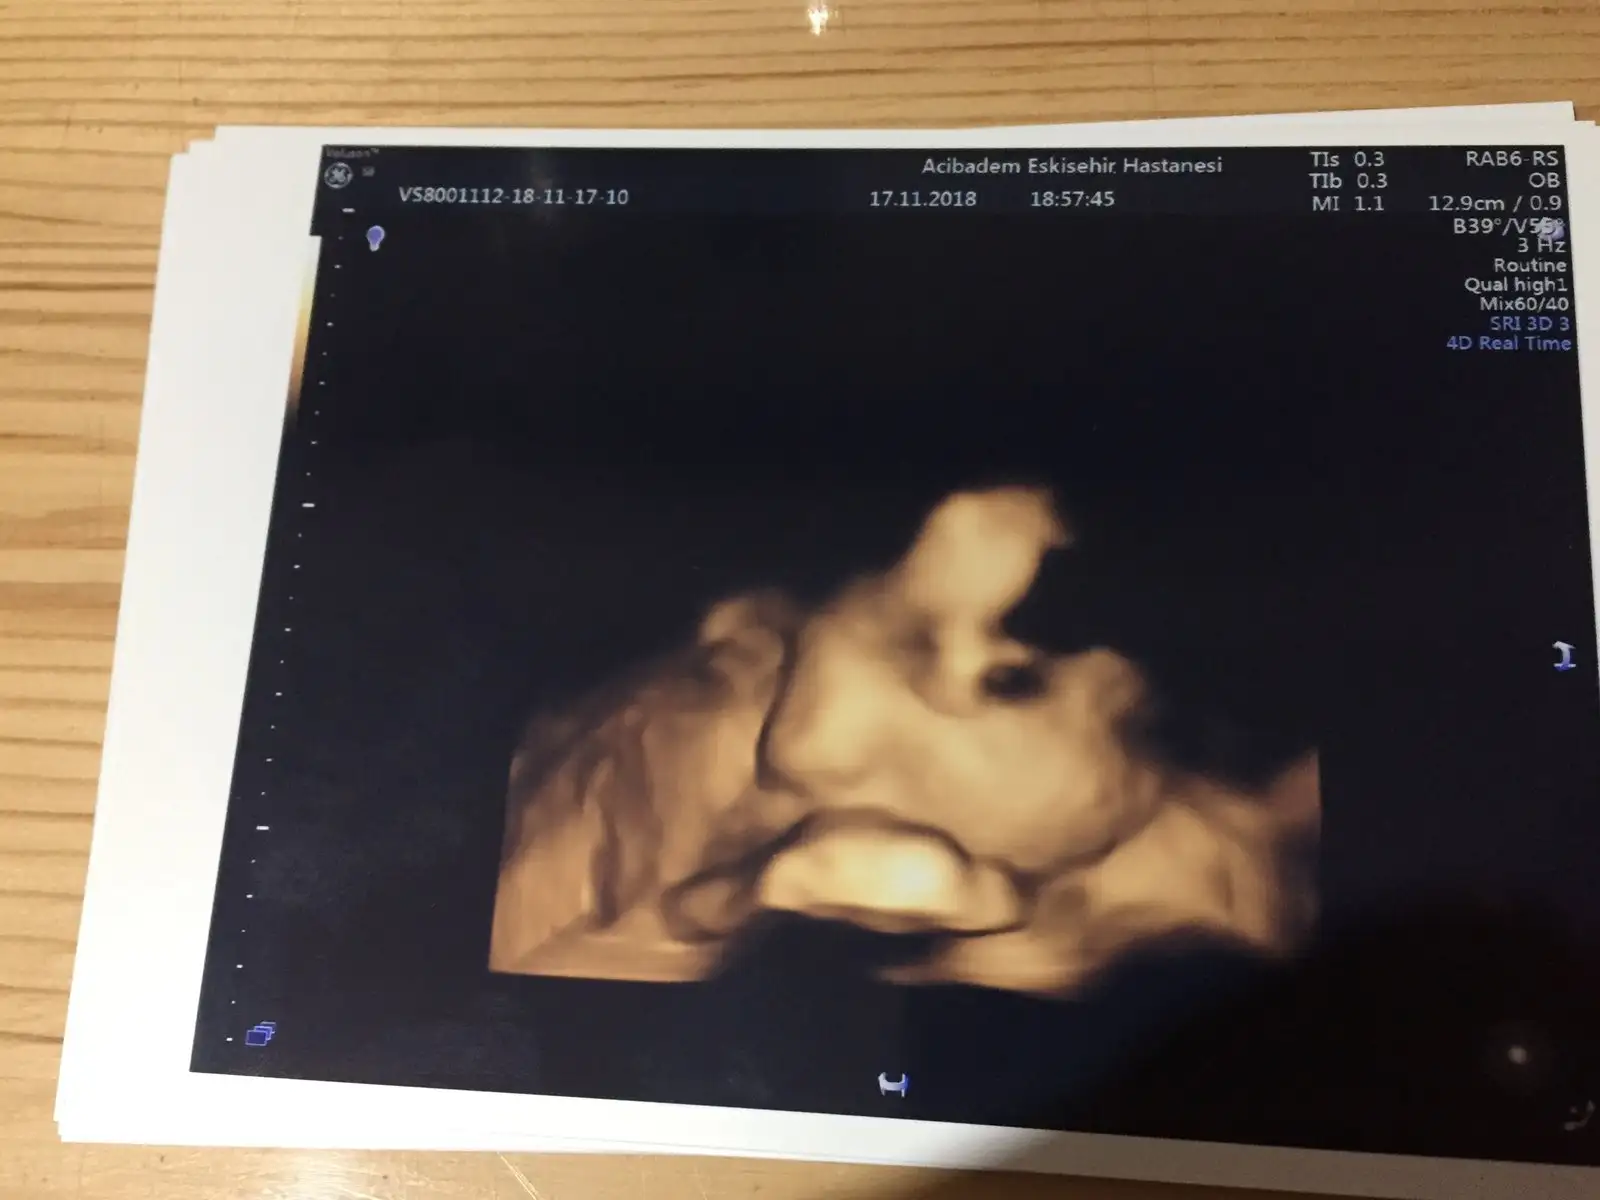

Oyyy minikkyaa bızım renklı pozlarımza bakın bugune dek bunları aldık 13haftalık biri dha 7cm orda

Bana da doktorum her gidişimde renkli görüntü verdi canım. Her defasında büyüdüğünü görmek çok güzel :)gecen bır arkadasıma da soyledım ankarada O. Ve gayet pahalı bır hastane. kadın renkli göstermemıs 17.haftada bıde dedım neden ses cıkarmıyorsun. ha şu da var benım hastaneme eşimın kuzenı gıdıyor o da daha alamamıstı onun dr.u baskası. nezaman verıyor dıye sordu bana benımkı verıyor dedım 13.haftadan buyana. dr.dan dr.a degısıyor demekkı canım![]()

evetttt yaaa resmen parmak kadarkenki halinden bebişliğe kadar olan sürecj göruyoruz nekadar şanslı bir donemdeyız kımbılır bızden sonra daha ne gelısmeler olacak şu teknolojide yerler onu pozlar hep aynı gb rahat glb ıcerde meleğinBana da doktorum her gidişimde renkli görüntü verdi canım. Her defasında büyüdüğünü görmek çok güzel :)